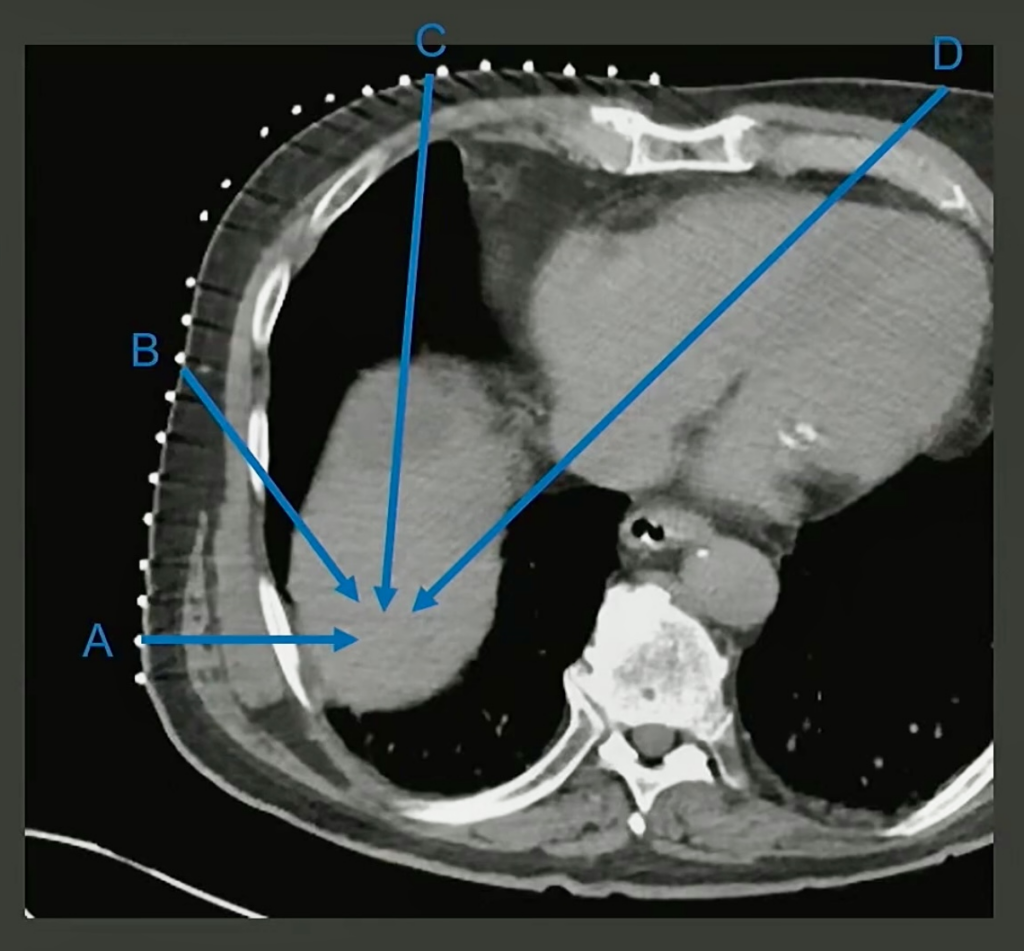

A. Bone

B. Bone

C. Lung

D. Heart (and cartilage)

…E. Call surgery?

Honestly, none of the above are particularly great. Bone is going to be hard, of course. No one wants to drill through the rib. You probably don’t want to go through the heart with an ablation probe either. You’ve got cartilage there, too.

The Solution: Instead of going through the lung—or, worse yet, calling surgery!—Aaltonen et al. opted to drop it. And by intentionally inducing a pneumothorax, they created a safe path to the lesion.